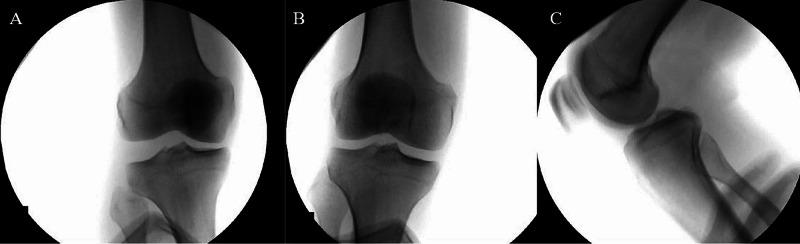

Bilateral knee dislocation is an extremely rare and devastating injury to the knee joint. This injury is a true emergency as concomitant injuries may threaten life and limb. Here, we report the case of a 26-year-old male patient who sustained bilateral knee dislocation due to a high-velocity motor vehicle accident. In this case, the patient suffered a feared complication associated with knee dislocation, popliteal artery disruption with peroneal nerve damage. Abdominal and skeletal injuries were also discovered and treated appropriately by a multidisciplinary team. A staged surgical approach to ligament reconstruction was used without any postoperative complication. Postoperatively, the patient successfully returned to his preoperative activity level.